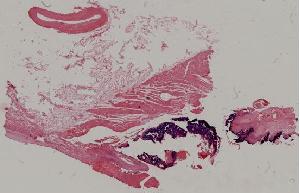

低倍视野